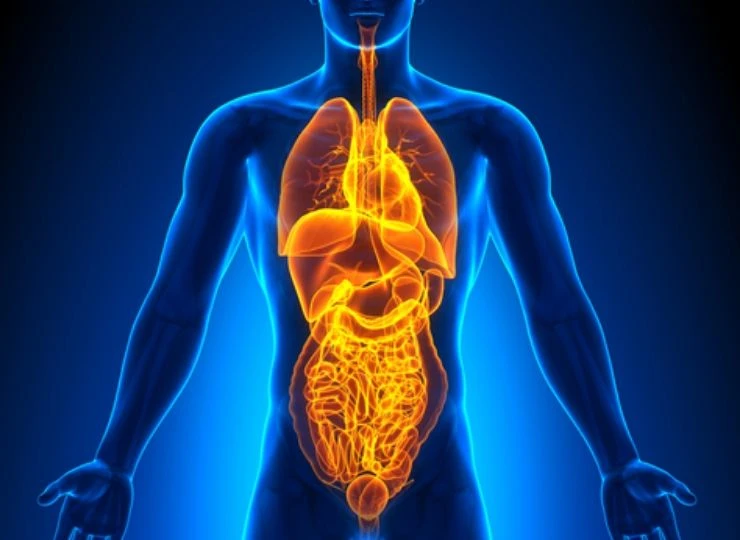

Brar Hospital is a Multi-Super Specialty hospital. It’s a hospital dedicated to excellent surgery care in the field of Weight Loss Surgery, Advance Laparoscopic surgeries, Stone surgeries, Gastrointestinal surgeries, Urological surgeries, Nephrology including Dialysis, Orthopedic surgeries, Critical care medicine and Gynecology.

Gastroenterology

Providing Services in Upper Gastrointestinal and lower Gastrointestinal endoscopic along with ERCP providing medical care for liver problems and Gastrointestinal problems